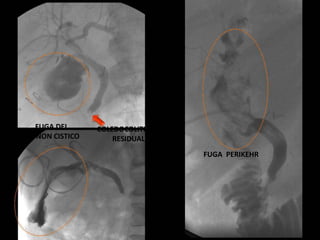

FUGA PERIKEHR

FUGA DEL

MUÑON CISTICO

COLEDOCOLITIASIS

RESIDUAL

FUGA PERIKEHR FUGA DEL MUÑONCISTICO COLEDOCOLITIASIS RESIDUAL